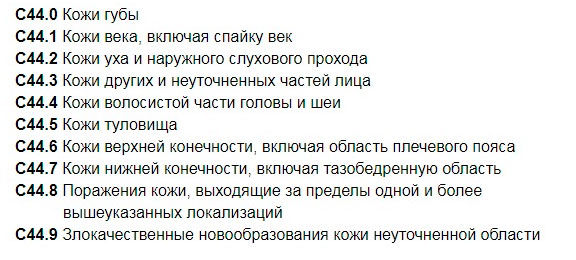

Код мкб 10 атерома головы

Код мкб 10 атерома головы 109 фото